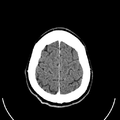

أشعة مقطعية للرأس توضح صورة المخ